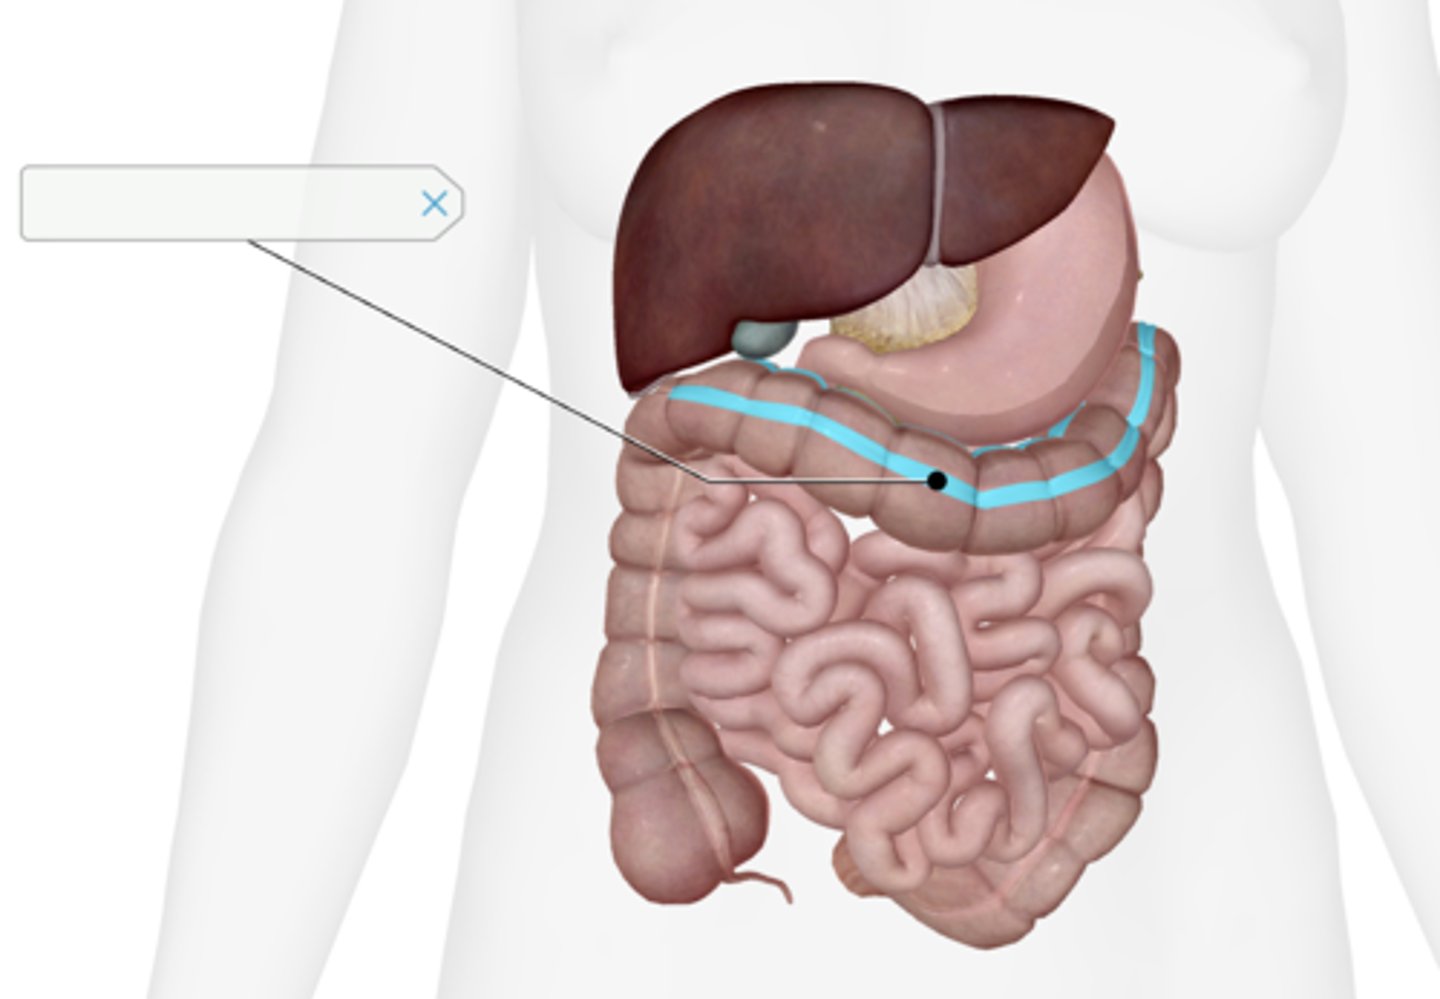

Transverse colon